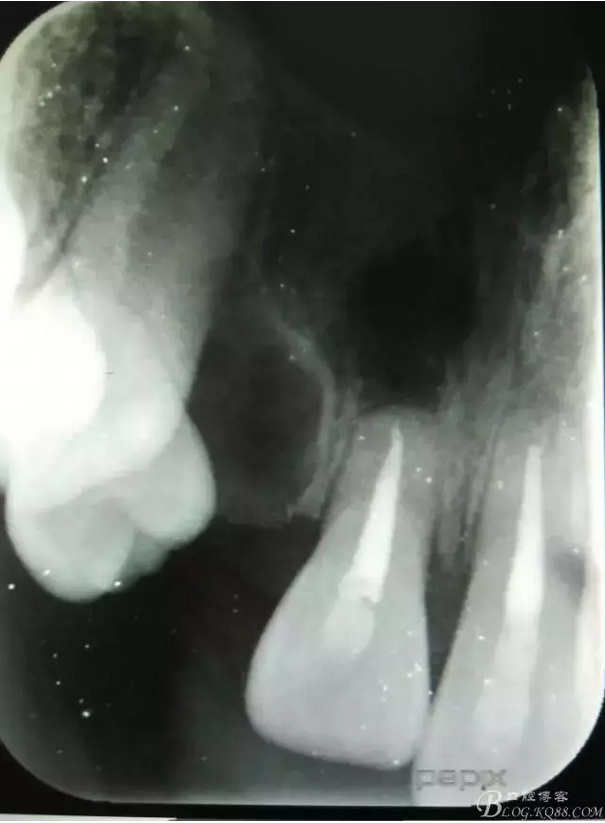

患者、李xx、男、15歲,主訴:牙不齊,矯正牙齒。??茩z查:發(fā)現(xiàn)11、21根尖三分之一折斷,患者否認有外傷史。正畸科治療建議如圖1.。術(shù)前簽手術(shù)同意書。